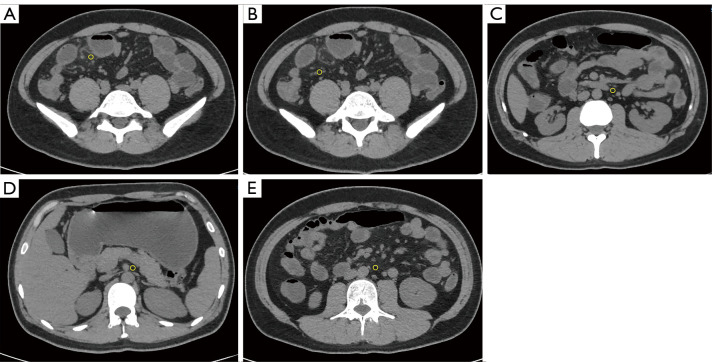

Background: Creeping fat (CF), a characteristic structure of Crohn's disease (CD), is closely associated with surgery and prognosis but lacks a unified imaging assessment standard, and endoscopic and serological indicators have limitations in evaluating extra-intestinal lesions. The study aimed to explore the correlation between computed tomography (CT) value distribution changes of mesenteric-surrounding fat in CD and disease activity.

Methods: In this study, we retrospectively analyzed CT enterography (CTE) images from 47 pathologically confirmed CD patients and 25 randomly selected controls with suspected inflammatory bowel disease (IBD). Quantitative measurements were obtained for mesenteric adipose tissue density (mean of CT values) along key anatomical landmarks including the mesenteric root, superior mesenteric artery, inferior mesenteric artery, perilesional regions, intestinal stricture, and adjacent branching vascular spaces. Other evaluated parameters included bowel wall thickness, CT attenuation, enhancement patterns, and CF grading. Qualitative evaluations were made by comparing with endoscopic, serological, and histopathological results and simplified CD activity index (CDAI) scores. A patient with concurrent anal fistula underwent magnetic resonance imaging (MRI) examination to compare its detection efficiency of fistula with that of CT examination.

Results: Significant inter-group differences were found in non-contrast mesenteric fat attenuation, mean ΔCT (difference in Hounsfield units between contrast-enhanced CT and non-contrast CT scans) enhancement, bowel wall thickening, mucosal enhancement, CF grading, intestinal stricture, and serological parameters (P<0.05). The moderate-to-severe activity group had the highest mesenteric fat density in the venous phase [mean ΔCT >20 Hounsfield units (HU), P<0.05], especially around lesions. There was a positive correlation between mesenteric fat CT values and images of diseased bowel segments. The mean value of the venous phase ΔCT of the lesion and the mean of the intestinal wall venous phase ΔCT value and intestinal wall stratification were positively correlated (>0.6, P<0.05). ROC analysis showed that the venous-phase ΔCT of perilesional adipose tissue had excellent diagnostic performance [area under the curve (AUC) =0.964] for moderate-to-severe activity CD, with 95.8% sensitivity and 87.5% specificity. The diagnostic efficacy of the venous phase in the vascular space around the lesion ranked second (AUC =0.943). MRI showed superior detection of the anal fistula to that of CT in one patient. Multivariate analysis confirmed it as an independent predictor for moderate-to-severe active CD (P<0.05).

Conclusions: Changes in mesenteric adipose tissue CT values and CF classification can distinguish CD from other IBD, suggesting their utility as another noninvasive diagnostic method for predicting the inflammatory activity of CD and evaluating the scope of surgery.